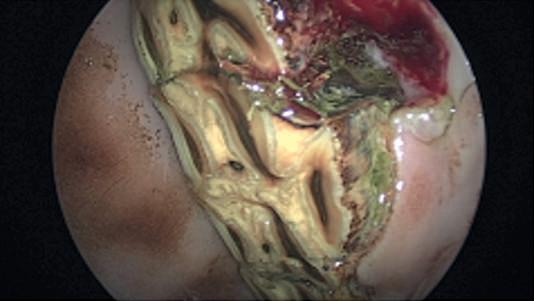

isan extensionoftheabdominallining.The vaginaltunicis incisedsothatthe testicleandepididymis canbe exteriorized. The testicleandepididymisareattachedatbothends,on onesideisa vascularportion containingthebloodsupply, attheotherendisanon-vascularportion containing the vasdeferens (tubethatsemenpassesthrough)and testicularligament.The vascularandnon-vascularportions areseparatedprior to transectingwithemasculators.

Followingasecondhibiscrub wash,andsurgicalspirit spray,thescrotumisasepticallyprepared forsurgery.The coltshouldnowbeheavilysedatedwithno feelinginthe scrotum.Asharpincisionismadeintoonesideofthe scrotumandtheassociated testicledropsout.The testicle andepididymisare containedwithina vaginaltunic–this

Emasculators arethespecialsurgical toolused for castrationinhorses.Theyprovidebothclampingandcutting actionatthesametime.Theemasculatorsareplacedon the vascularportionfirstandheldinplacefor3–5minutes to ensuregoodclottingwithintheblood vessels.The emasculatorsarethenplacedonthenon-vascularportion for aminute to detachthe testicleanditsassociated structures entirely.Thesameprocedureisthen carriedoutonthe othersideofthescrotum to remove thesecond testicle. Following castrationthere shouldnotbeanythinghanging outoftheincisions,butthere maybeasmallamountof blooddripping.Aslongas you can countthedrips(not so fast as to create a streamofblood)thenthisisnotof any concernandwill stopshortlyaftertheprocedure. We generally recommendthatthegelding remaininthe stable (or verysmallpaddock) forthenext12– 24 hours